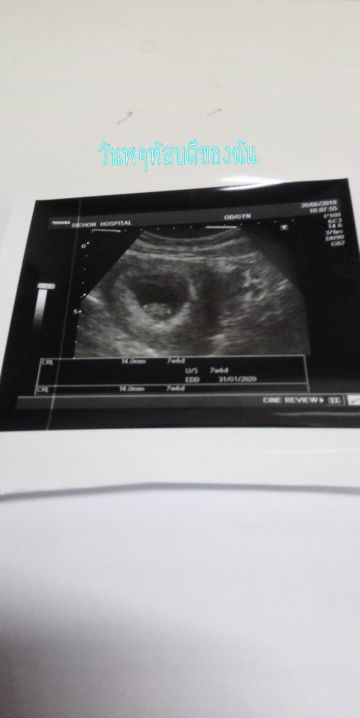

4ปีแห่งการรอค่อย หนูน้อย??

แต่งงานมา4ปี มีหลายคนถามเรา อยากมีลูกไม่ เราบอกรอเค้าให้มาเค้าไม่มา วันที่ตรวจเกือบช็อค? ในที่สุดเทอก้มา 4ปีที่รอ. ตอนนี้11สัปดาห์ 1วัน เป็นความรุ้สึกอธิบายไม่ถูก ดีใจจนน้ำตาไหล ตอนนี้รู้แค่ว่ารักทุกอย่างทำเพื่อเทอเด้กน้อย ❤❤